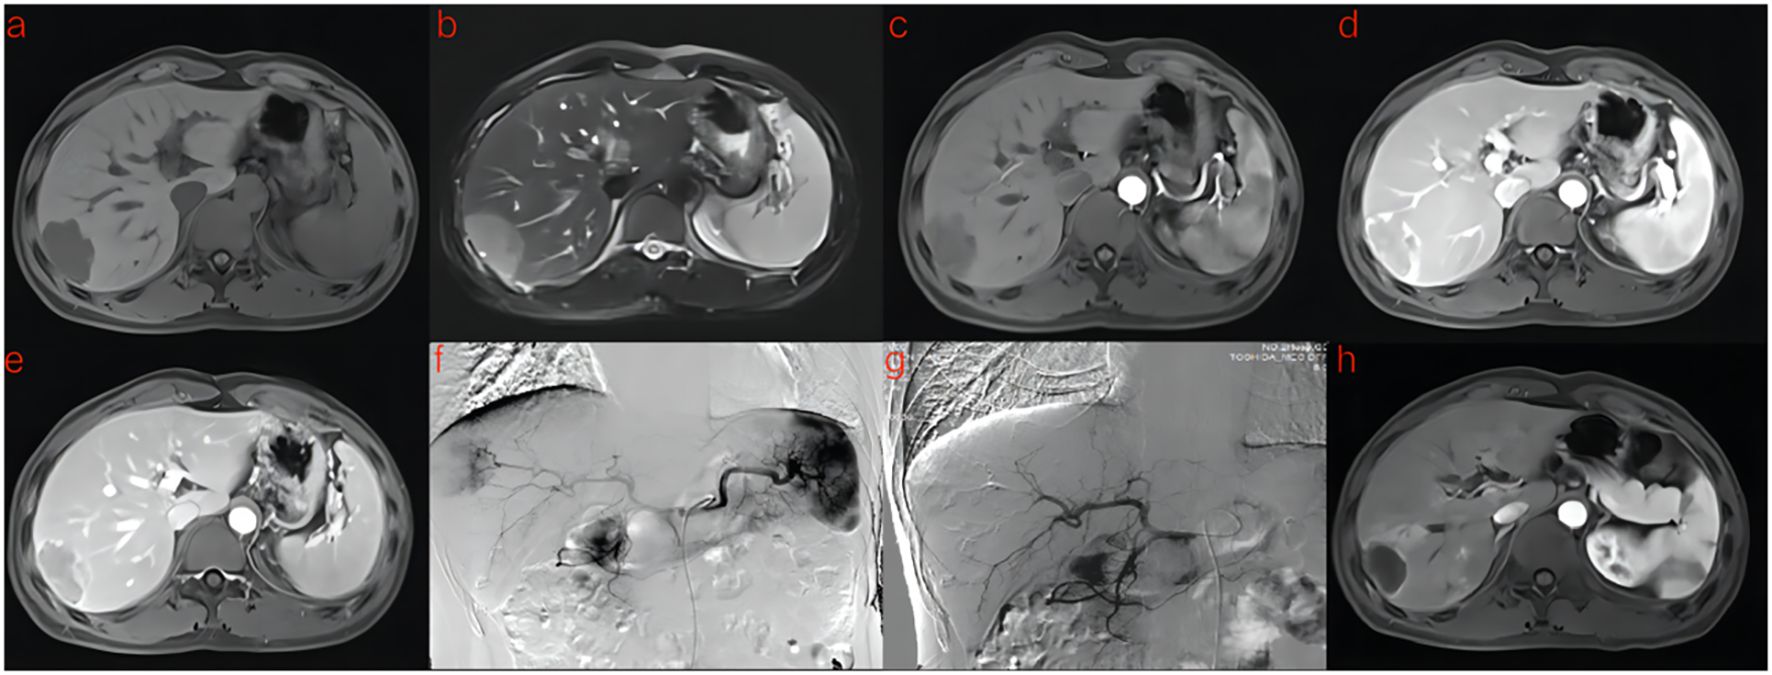

A flowchart of the study is shown in (Figure 2). The baseline clinical characteristics and demographics of the training and validation groups are summarized in (Table 1). The enrolled patients were allocated to a training set (n=114) or an external validation set (n=43). The efficacy of DEB-TACE was balanced for patients in the two cohorts, with early peritumoral recurrence rates of 40.3% (n=46) and 46.5% (n=20) for the training and independent external validation cohorts, respectively. Images of the two patients are shown in (Figure 3) and (Figure 4). No significant differences were detected in sex, age, ALT, ChildPugh, HBsAg, cirrhosis, portal hypertension, tumor number, tumor margin, rim enhancement, or peritumoral enhancement between the recurrence and non-recurrence groups (P>0.05). Moreover, the AFP levels (P = 0.031) were significantly different between the two groups in the training cohort. AST level (P = 0.015), tumor size (P = 0.002), and BCLC stage (P = 0.016) also showed statistically significant differences in the external validation cohort. AFP in the training cohort was constructed for the clinical model (Table 1).

Figure 4. A 41-year-old man with HCC was treated with DEB-TACE. (a–e) MR examination revealed that the tumor was located in the segment 7 of the liver. (f) The tumor supplying artery was the hepatic arteria 7. (g) The tumor supplying artery was embolized by 300-500 μm pirarubicin-loaded beads. (h) One months later, MR Enhanced follow-up examination showed abnormal enhanced tumor recurrence.